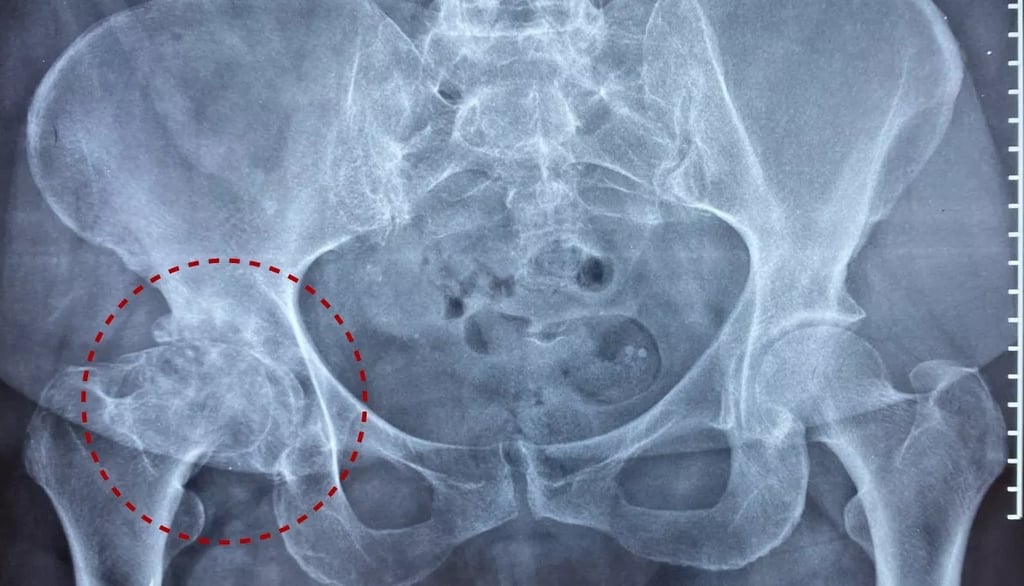

La osteoartritis se caracteriza por el "desgaste" de las articulaciones del cuerpo debido al envejecimiento normal, pero puede acelerarse y aparecer antes en la vida debido al uso excesivo intenso y repetitivo de estas articulaciones. Factores como los genes, el peso y los antecedentes de lesiones o accidentes de las articulaciones también pueden provocar osteoartritis. Afecta con mayor frecuencia a las caderas y las rodillas, pero la columna, las manos, las muñecas y los tobillos también suelen ser áreas problemáticas. El desgaste provoca el adelgazamiento de los discos o cartílagos entre las superficies óseas de las articulaciones y la fricción posterior. El dolor, la inflamación y los depósitos óseos (osteofitos) resultantes de esto hacen que el tejido blando circundante se acorte y la persona reduzca el uso de la articulación. Esta movilidad reducida priva a la articulación de una lubricación, drenaje y nutrición adecuados y los músculos alrededor del área pueden inhibirse y debilitarse.

Mantenga una actitud positiva: recuerde que las investigaciones muestran que un gran número de personas con artritis que se muestran en radiografías o resonancias magnéticas no presentan ningún síntoma. ¡Vos podrías ser uno de ellos!